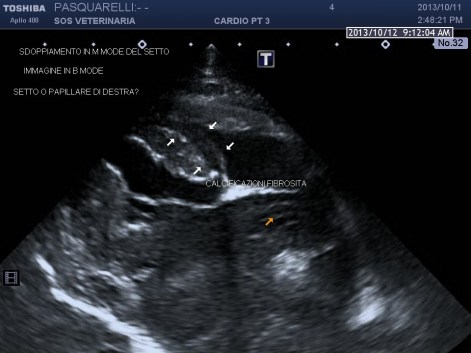

Per avere una idea del grado di pericolosita’ della malattia basta visionare lo smoke (effetto fumo) nell’atrio sx del soggetto e il voluminoso trombo fluttuante e martellante i lembi valvolari .

caso di cardiomiopatia ipertrofica del Maine Coone ,presentazione al pronto soccorso tipica con edema polmonare e tromboembolismo aortico completo bilaterale ,per la mia esperienza,nessun trattamento risulta essere efficace per questi soggetti, il decesso avviene nel 90%-95% dei casi e quelli che sopravvivono muoiono nelle settimane successive per le severe complicanze provocate dall’ipoperfusione ,i trattamenti trombolitici non risultano praticabili per diverse ragioni, non ultima quella economica, l’evento drammatico non e’ lo scompenso cardiaco diastolico (sul piano farmacologico gestibile) ma la trombosi aortica spesso anche polmonare .